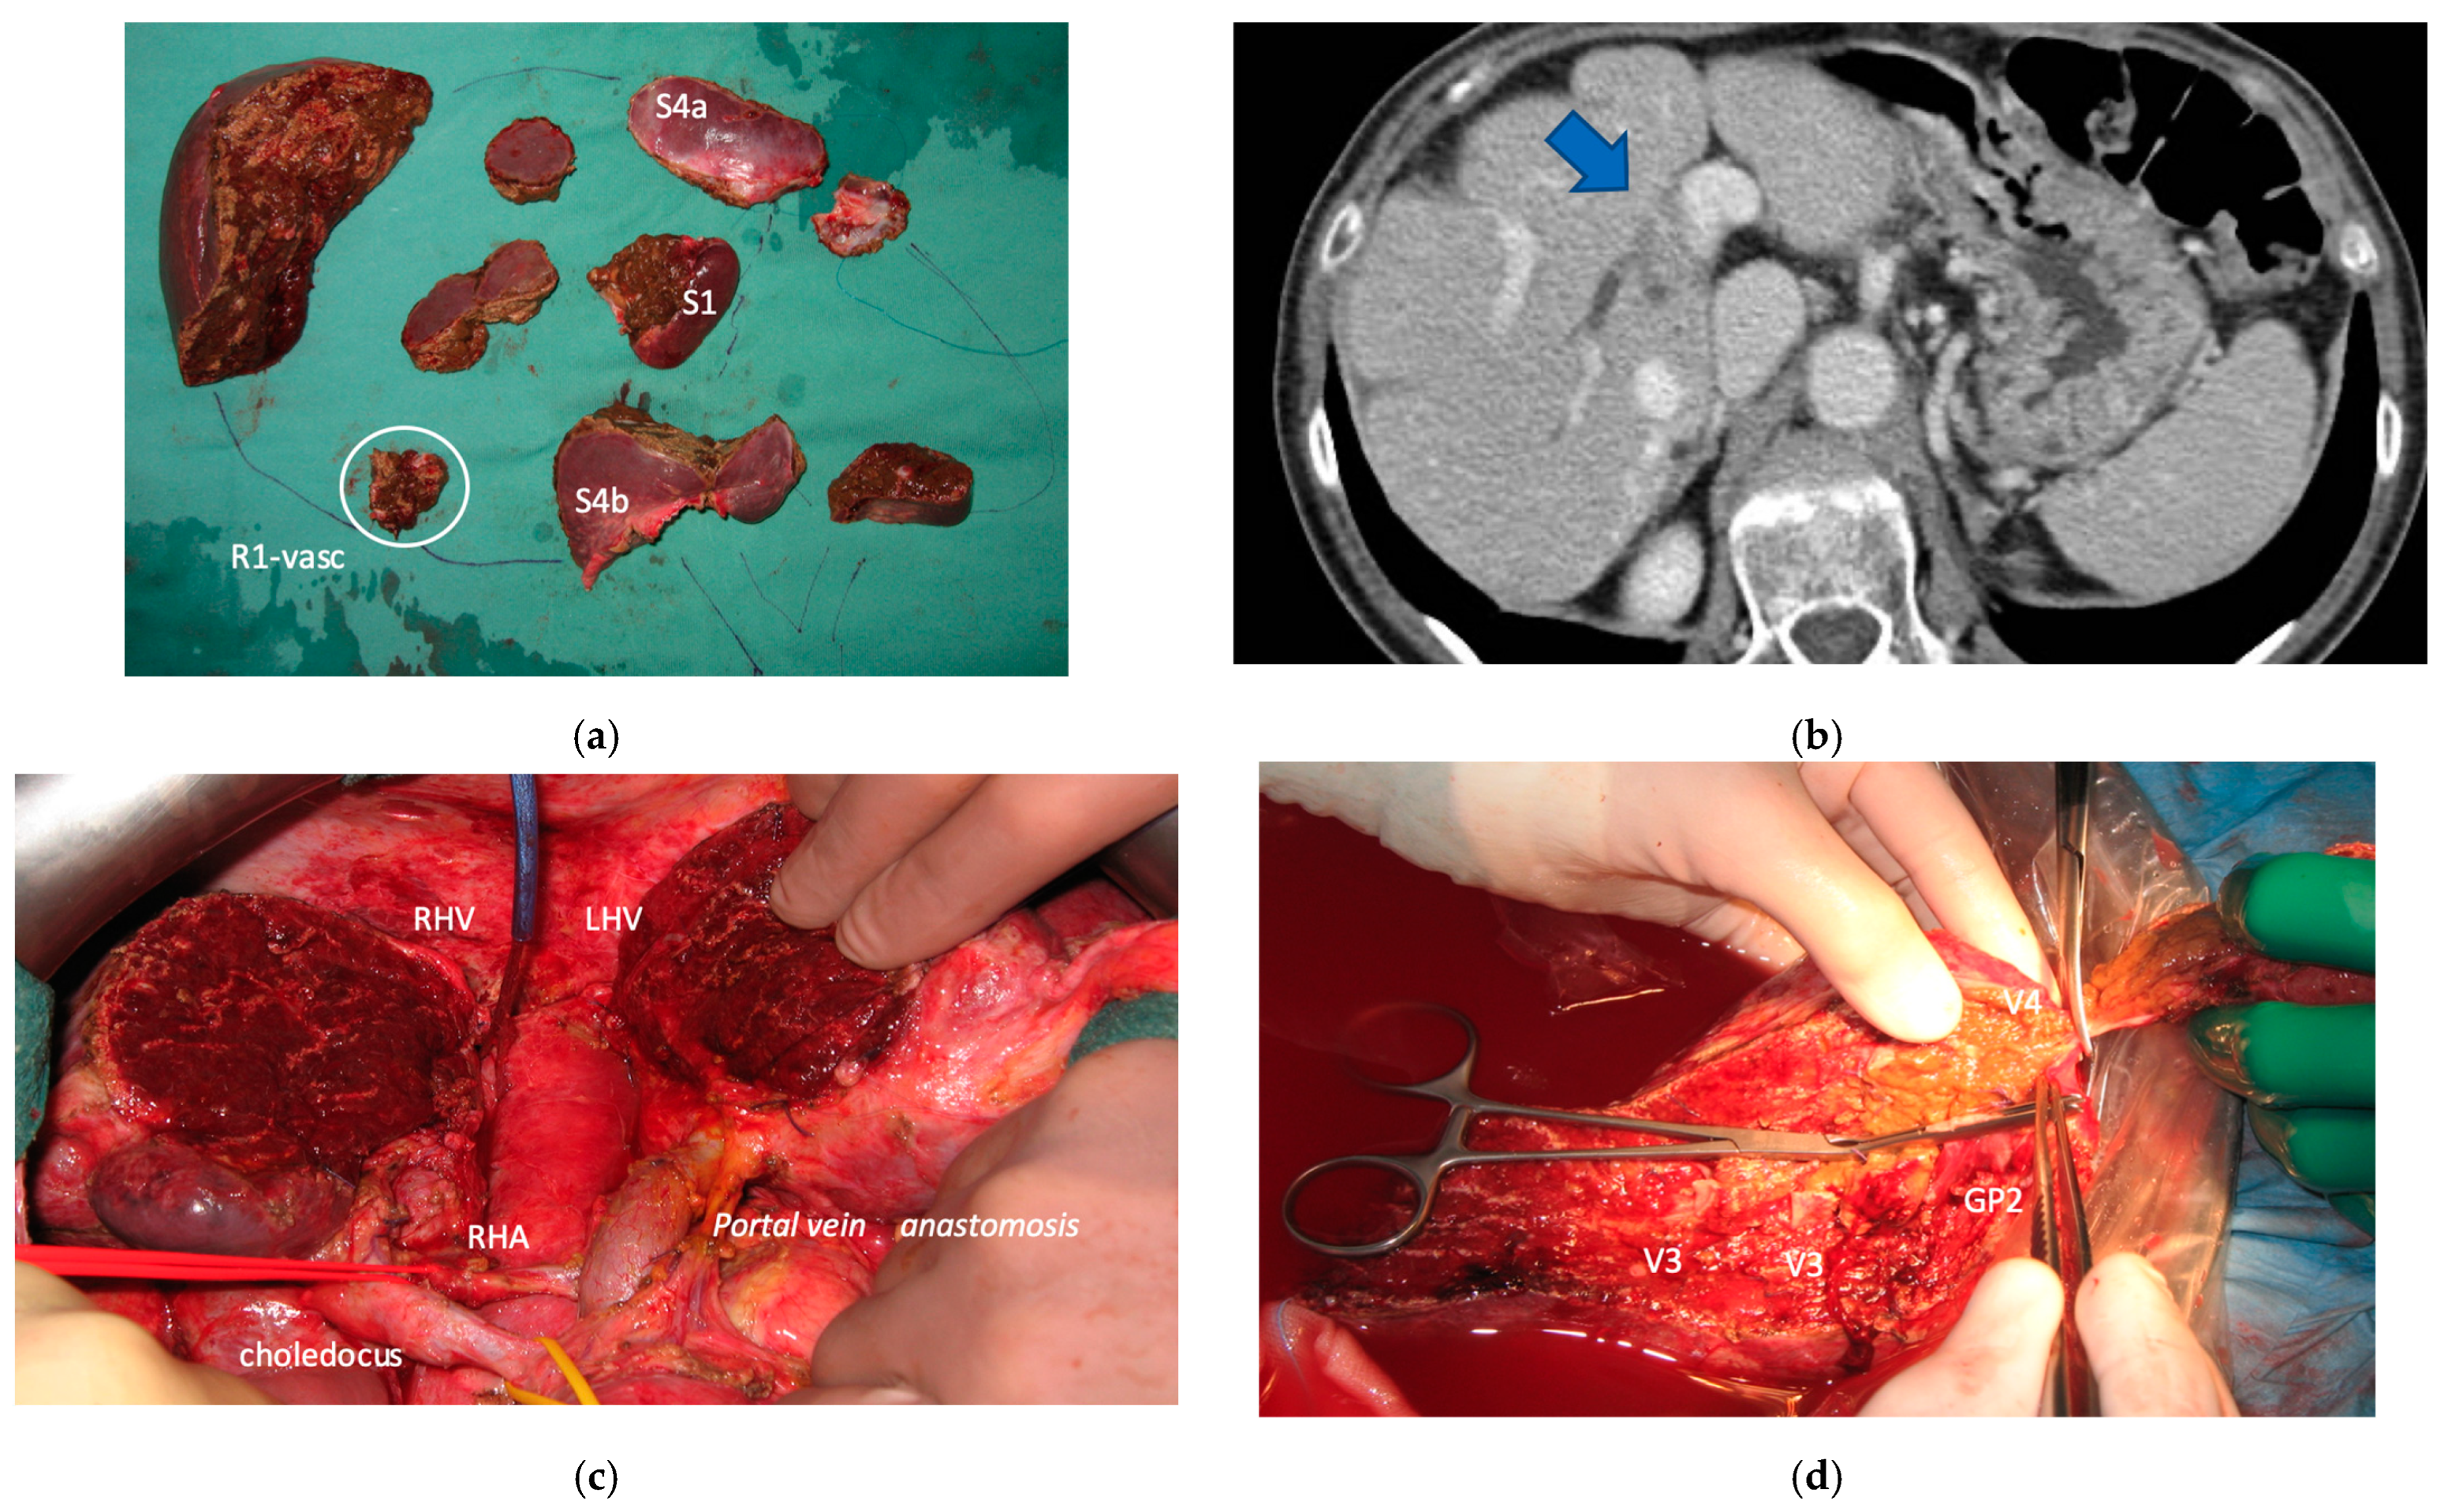

Liver partition was obtained with a major mesohepatectomy in two cases with anatomical resection of S1/S4/S8 (en-bloc with biliary tree in one, see Figure 5).

3.5. Surgical Reconstructions

Biliary tract was reconstructed in two cases. In one case of MLP of S1/S4/S8 extrahepatic biliary tract was resected up to b5, left duct and posterior duct (Figure 5) and reconstructed with a three-duct jeujunostomy. In the other case, left-duct jeujunostomy was performed at the first stage of e-ALPPS simultaneously with portal vein resection and reconstruction with an end-to-end anastomosis.

3.6. Histology

One MLP (resection of S1/S4a) was R1, all other liver resections including the intermediate stage of e-ALPPS and all the second/third stages were R0.

Two out of eight patients with unresectable disease relapse are still alive although with evident disease: one patient 18 months after e-ALPPS performed as a “liver first” strategy for 27 synchronous CRLMs with left colon adenocarcinoma and interaortocaval lymph nodes, then followed by a left hemicolectomy and interaortocaval lymphadenectomy, who experienced an extrahepatic recurrence 3 months after surgery; and one patient 38 months after a major MLP associated with a three-duct jeujunostomy (performed for two CRLMs infiltrating the confluence of left and right bile ducts up to S8 bile duct and with modest dimensional increase of CRLM after 47 cycles of FOLFIRI + Bevacizumab across several reintroductions, Figure 5), with hepatic and extrahepatic recurrence 12 months after surgery.

Three patients died. One (11%) of the nine patients who completed the liver augmentation strategy died within 90 days of completing the strategy (at 2.3 months). This patient had a diagnosis of right-sided colon cancer with 67 synchronous CRLMs and achieved stable disease after six cycles of FOLFOXIRI + bevacizumab. He was treated with an e-ALPPS, and after the first stage of MLP and simultaneous right hemicolectomy developed an asymptomatic thrombosis of the common trunk of the portal vein. After a high dose of heparin, FLR volume increased up to 39%, the second stage of e-ALLPS was complicated by severe liver failure, the patient was discharged from the hospital but died with liver failure and lung disease progression. The other two patients died due to disease recurrence. One patient with five synchronous CRLM from rectal adenocarcinoma experienced disease recurrence 2 months after surgery and died 20.5 months after MLP. The third patient had a previous e-OSH with detachment from the right GP of one of the 20 synchronous resected CRLMs. Four months after e-OSH a local disease recurrence occurred at the site of detachment with infiltration of the right biliary duct. Since disease recurrence was stable after 8 cycles of FOLFOXIRI + Bevacizumab and other 13 cycles of maintenance chemotherapy, an e-ALPPS (FLR = residual S2/S3/S4b) with portal vein and biliary resection/reconstruction was offered. Eight months after e-ALPPS, a new recurrence occurred in S2 infiltrating the LHV at the hepatocaval confluence and GP for S2. This new disease recurrence was stable after three cycles of FOLFOXIRI + Bevacizumab followed by 4 cycles of FOLFIRI + Bevacizumab. A monosegmental auto-transplantation was proposed (FLR = S3/S4b increased after e-ALPPS up to 769 mL corresponding to a graft-to-recipient body weight ratio of 1.37) and performed with success but it was complicated by a late biliary leak and the patient died of sepsis 92 days after liver auto-transplantation, 16.5 months after e-ALPPS (see Figure 15).